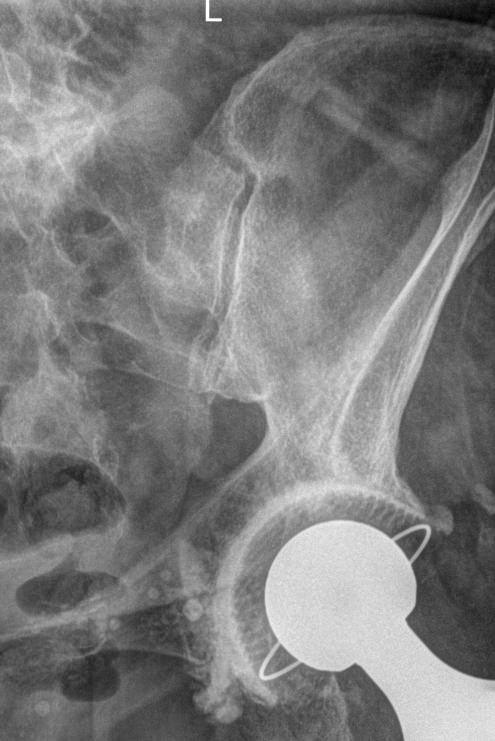

Для диагностики сочленения прибегают к рентгенографии, причем снимки делают с обеих сторон, чтобы можно было сравнить здоровую и измененную сторону. Для более детального исследования применяют МРТ.

Что покажет рентген крестцово-подвздошного сочленения?

• Изменения в состоянии рентгеновской суставной щели ― расширение, сужение, сращение;

• Изменения суставной поверхности ― нечеткость контуров, уплотнение, эрозии;

• Изменения в костной ткани ― участки деструкции, воспаление, склероз;

• Наличие кист и других новообразований;

• Изменения в мягких тканях